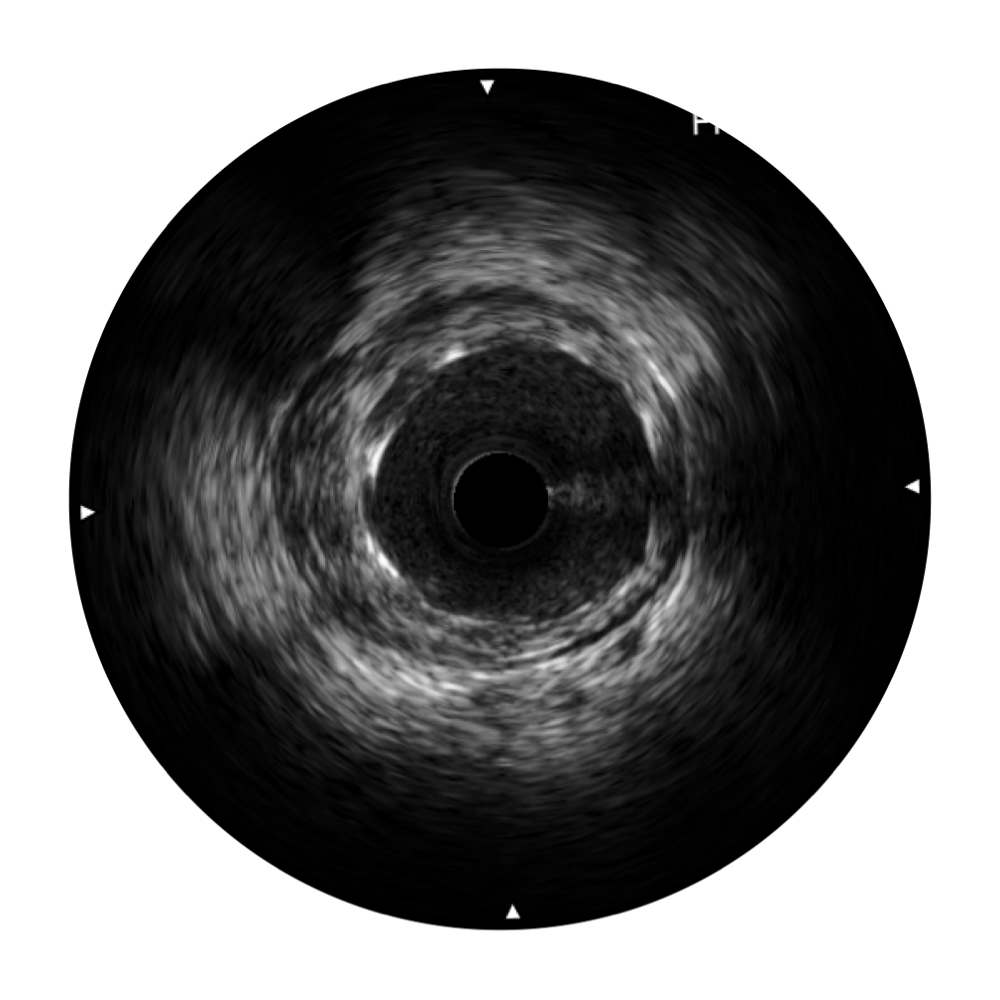

db真人体育官网宽频IVUS图像

传统IVUS图像

对比传统IVUS导管成像,db真人体育官网宽频IVUS图像的近场支架梁显影更细腻,远场中膜外血管仍清晰可辨,兼顾远中近,兼顾分辨力与穿透深度